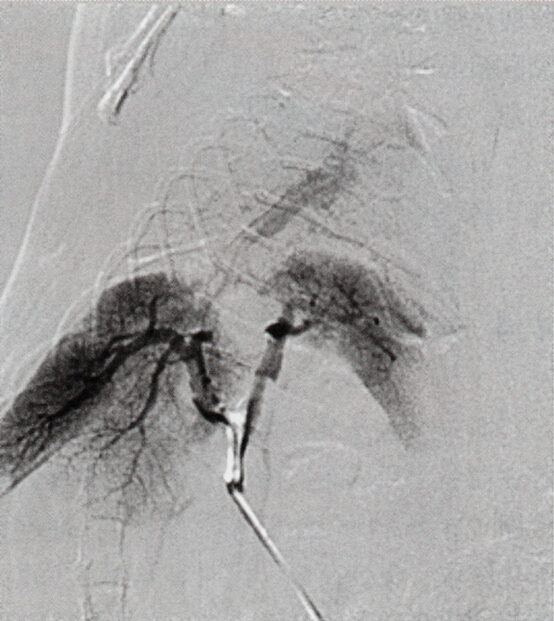

图4-4 A:大鼠双肝移植后肝静脉系统DSA检查,显示门静脉、肝静脉通畅。

图4-4 B:大鼠双肝移植后肝胆管系统DSA检查,显示胆管系统是通畅的